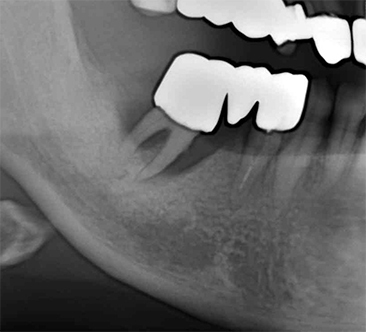

インプラントのレントゲン写真

治療期間約5ヶ月

右下のブリッジを支える歯が重度歯周炎でグラグラになり抜歯となりしました。炎症が治まった後、薄くなった骨を広げてインプラント治療しました。

Dさんの場合大きくかかる料金は、

手術料 フィックスチャー埋入術ZIMMER Spline TwistTM 200,000円

(220,000円税込み)

スプリットクレスト法 78,000円

(85,800円税込み)

アバットメント料金 既製バットメント 45,000円

(49,500円税込み)

クラウン料金 メタルバッキング

ハイブリッドクラウン

75,000円

(82,500円)

合計 398,000円

(437,800円税込み)

(一本分)